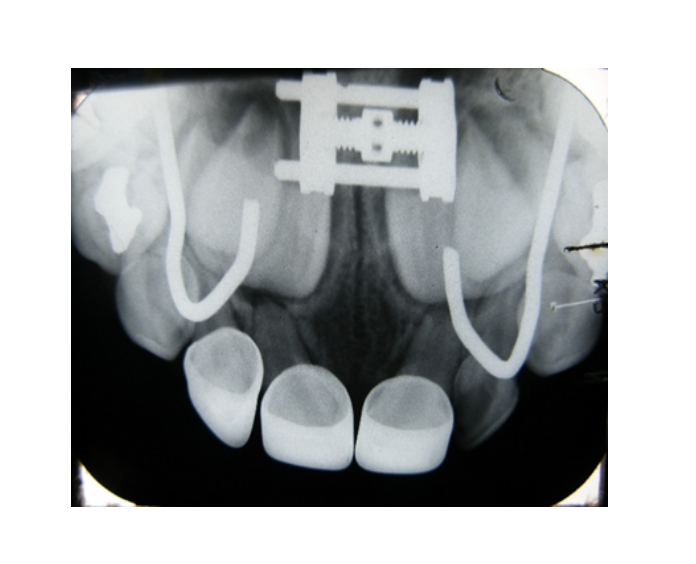

Contamos con equipo radiológico de tomografía dental, siempre a la vanguardia para diagnosticar cada problema dentofacial. Atendemos desde recién nacidos, hasta adultos mayores a los cuales se les trata con profesionalismo, calidad, experiencia, honestidad y puntualidad.

Tomógrafo Dental

Ray Scan